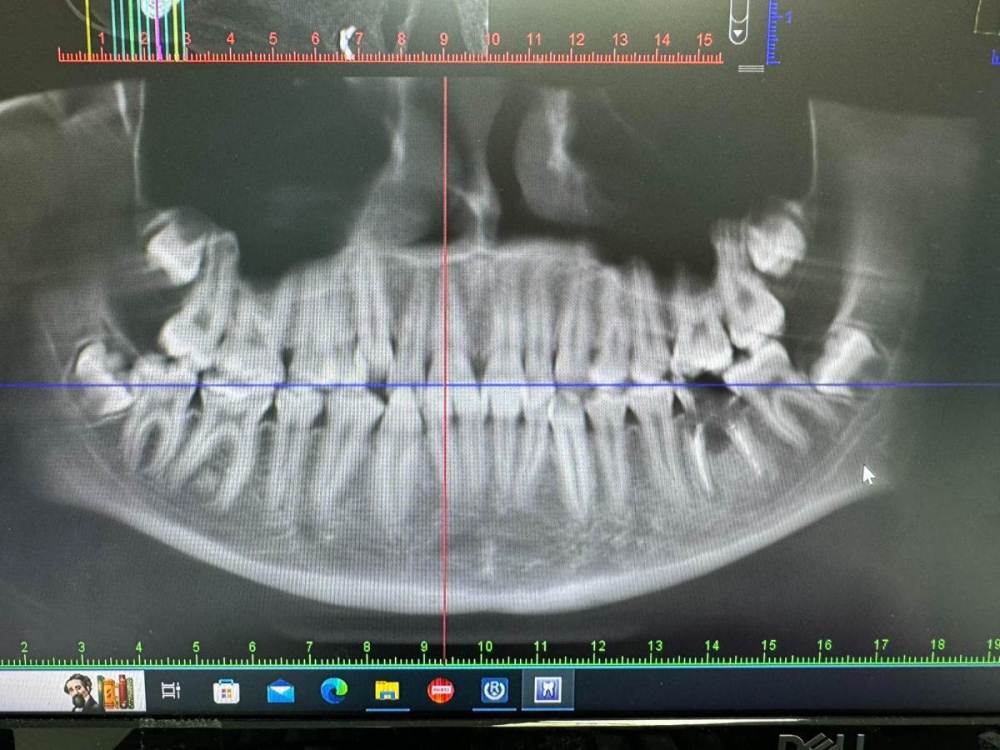

Петрович Опубликовано 4 февраля, 2024 Поделиться Опубликовано 4 февраля, 2024 Чтобы они не вредили нижним 7. Планируется: брекеты и имплантация 3.6 через год - в 14 лет. Ссылка на комментарий

Bier Опубликовано 5 февраля, 2024 Поделиться Опубликовано 5 февраля, 2024 планируется ортодонтия, 8ки мешают по плану лечения. После формирования корней - удаление будет сложнее и риск осложнений вырастет. 1 Ссылка на комментарий

Bier Опубликовано 5 февраля, 2024 Поделиться Опубликовано 5 февраля, 2024 ну еще действует аргумент, что они сейчас мешают дистализации зубов. Еще аргумент: могут быть причинами рецидива ортодонтического лечения. Удаляю такие зачатки часто. 12-16 лет пациентам. Ссылка на комментарий

Петрович Опубликовано 8 февраля, 2024 Автор Поделиться Опубликовано 8 февраля, 2024 Бывает хочется вырвать и всё. И камни почистить чтобы зубы гладкие были. Встречаются люди, которым камни лучше не снимать. @Женька профилактикой клиновидных дефектов ещё надо заниматься. Камни обычно хочется убрать, когда зкбы@Женька 06.02.2024 в 10:49, Женька сказал: Отнюдь, Вы же доктор, Вы знаете прогнозы, риски и тд. Впрочем коллеги и я выше уже всё расписали. Аналогия с покрытием коронками депульпированных и сильно разрушенных зубов. Вы же знаете, что если не покрыть коронкой, рано или поздно произойдёт скол, возможно под десну, и зуб на удаление. И также решаете проблему, которой пока ещё нет. Коронки для профилактики не прижились. Чаще обходится закруглением стенок и перекрытием бугров. Если бы сам был ортопедом. Или если бы он был рядом и не требовал штифтования. Тот же пациент. Ссылка на комментарий